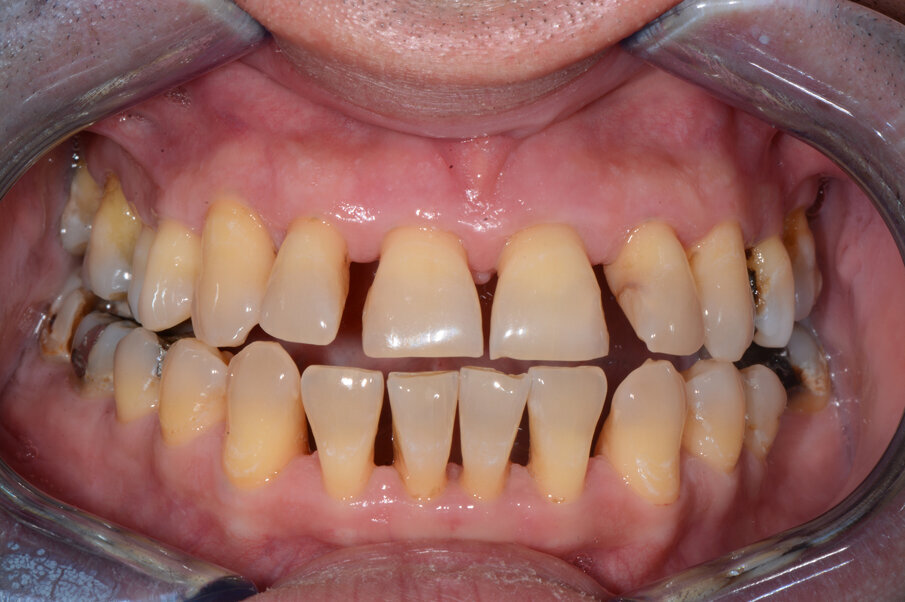

Pacijent starosti 29 godina, s agresivnom formom parodontitisa. Pacijent je u trajanju od 2 godine lečen nehirurškom, a zatim i hirurškom terapijom oboljenja parodoncijuma uz primenu preparata GelCide. Nakon 2 godine, pacijent je protetski rehabilitovan fiksnim protetskim radom.